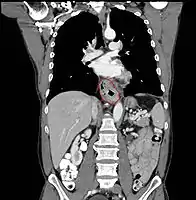

- Lower thoracic esophagus and EG junction:

- Inferior pulmonary veins to the stomach; includes the intraabdominal portion of the esophagus

- By endoscopy, 30 to 40 cm

- For cancers arising near the EGJ, they are staged as esophageal/EGJ if the epicenter is in the lower thoracic esophagus, the EGJ, or within the proximal 5 cm of the stomach (cardia) and extend into the EGJ or esophagus

- Those with an epicenter in the stomach greater than 5 cm distal the EGJ, or those within 5 cm of the EGJ but that do not extend into the EGJ or esophagus, are staged as gastric